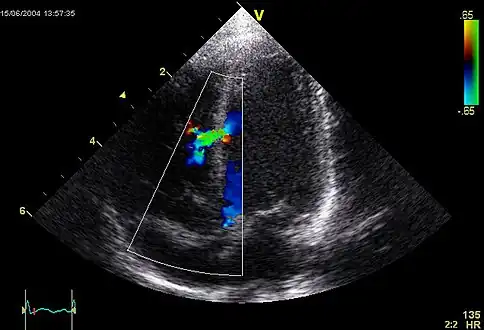

Doppler resolved this problem by visualizing the retrograde flow in the MPA , indicating pulmonary valve atresia

Ventricular septal defect via echocardiogram